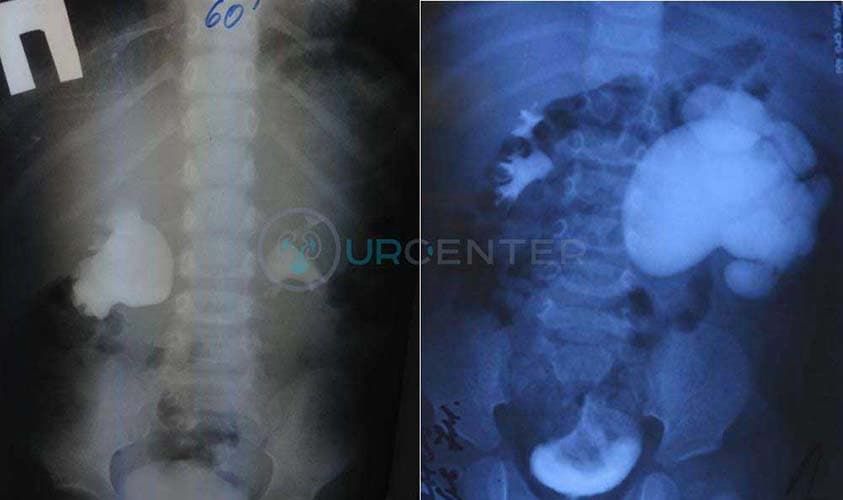

Экскреторная урография необходима для визуализации чашечно-лоханочной системы почки, определения нарушения оттока мочи. При этом после биохимического исследования крови (мочевина, креатинин) внутривенного вводится йодсодержащий контраст в возрастной дозировке и выполняется серия снимков. На снимках определяется коллекторная система почки, мочеточник, мочевой пузырь. По степени расширения лоханки и чашечек, а так же по времени контрастировани полостей и скорости выведения контраста судят о выраженности гидронефроза.

Урография

- Стоимость: 5 000 руб.

- Продолжительность: 45 минут

В качестве дополнительных методов диагностики применяют внутривенную урографию, цистографию, радиоизотопное изучение почек.